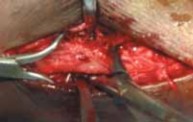

2. Following exposure of the fracture, the first step involves cleaning the fracture site (

TECH FIG 2A

), followed by fracture reduction.

3. Usually reduction is afforded by a small “lion jaw” clamp or pointed reduction forceps.

1. If reduction is difficult, manual traction with prona-tion and external rotation will afford fracture alignment in supination–external rotation patterns.

2. Care should be taken to avoid placing clamps over fracture spikes to prevent inadvertent comminution (

TECH FIG 2B

).

1. If the clamps make it difficult to place a lag screw, provisional Kirschner wires may be placed across the fracture and the clamps removed (

TECH FIG 2C

--- TECH FIG 2 • A. Cleaning the fracture site with a small curette. B An example of clamp placement across the fibular fracture site. Care is taken not to comminute the fracture spike. C. Lag screw placement, overdrilled with a 3.5-mm bit proximally. D. This is followed by drilling of the far cortex with a 2.5-mm drill. E. A neutralization plate is applied to the lateral surface of the fibula. F. Example of distal screw pen- G etration to be avoided. G. Wound closure. ANTEROMEDIAL APPROACH TO THE MEDIAL MALLEOLUS Exposure 1. The medial malleolus is approached via a gently curved anteromedial incision (